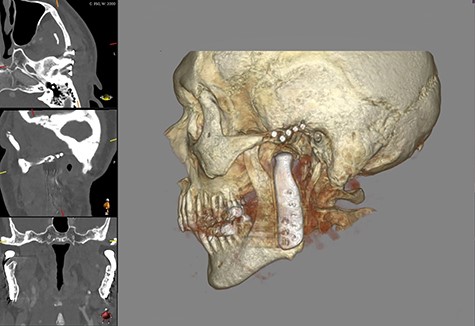

CT scan showing radiological signs of loosening of the left fossa component. On the left, the presentation of the periprosthetic edema (A), fracture of an osteosynthesis screw (B) and the osteolysis around the screw shafts (C).